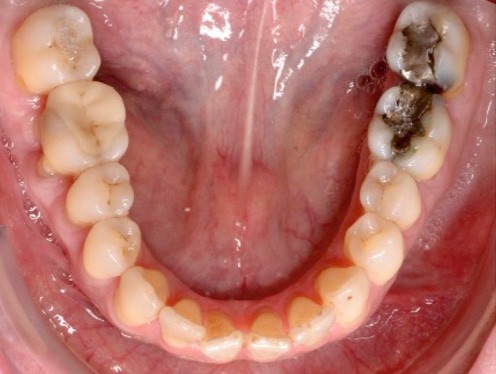

À l’examen endo-buccal (fig. 2), on note une formule dentaire complète (absence des 8) avec présence de restaurations multiples étanches, un bon contrôle de plaque et une parodontite de stade 4 grade C stabilisée [3], des récessions gingivales et des mobilités dentaires généralisées (degré 2, classification de Miller). L’arcade mandibulaire présente une courbe de spee importante avec égression du bloc incisivo-canin. Les milieux inter-incisifs sont alignés, le recouvrement est normal, le surplomb est augmenté à 3 mm et associé à des diastèmes et de la vestibulo-version des incisives maxillaires. Les relations antéro-postérieures canine et molaire sont en Classe I d’Angle.